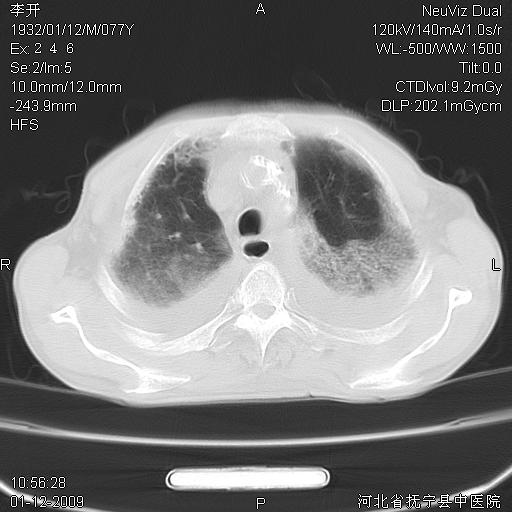

以下是引用黑白光影在2009-1-19 16:49:00的发言:[br]心衰肺水肿;心包、胸腔积液;冠脉钙化;肺部感染。